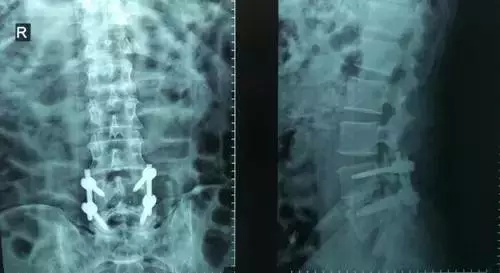

劉志安副院長所說的“微創(chuàng)小切口”就是通道下髓核摘除植骨融合經皮內固定術。其原理就是利用MIS-TLIF技術微創(chuàng)治療腰椎疾病,不但能達到開放手術的效果,且切口及創(chuàng)傷為開放切口的1/3,術中出血量少,患者術后可以恢復更快。

劉志安副院長將具體的手術過程向朱先生做了介紹,朱先生也同意了這個“微創(chuàng)小切口”手術。于是在術前的精心準備之后,劉志安副院長協(xié)同其他醫(yī)護人員為朱先生進行了手術。術后,朱先生的切口愈合良好,腰部疼痛消失,小腿麻木感也漸漸緩解。“手術后傷口略微有點痛,現(xiàn)在已經完全不痛了,這種輕松的感覺已經好久沒有了,真是萬分感謝劉院長。”在病房內,一臉笑容的朱先生如是說。

據(jù)劉院長介紹,MIS-TLIF技術是經椎旁肌間隙入路運用脊柱內鏡或專用通道行腰椎間盤切除、椎管減壓、植骨內固定術,是一項應用廣泛、技術成熟的脊柱微創(chuàng)手術方法。本技術可以完成與傳統(tǒng)手術完全相同的椎間盤切除、椎間植骨融合內固定等操作。手術切口一般3-5厘米,本手術方式可有效避免傳統(tǒng)手術對腰背肌肉的損傷,患者術后腰背部疼痛輕、恢復快,手術效果優(yōu)于傳統(tǒng)手術,治療后1-3天即可下床活動。本技術適于大部分的腰椎間盤突出癥、腰椎管狹窄癥、腰椎滑脫癥等。